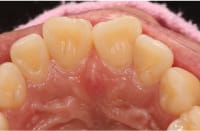

• Case3

前歯のずれが気になる

Before

After

年齢

30代女性

治療期間・回数

約3ヶ月間、6回

費用

総額550,000円(税込み)

(検査・診断・マウスピース費用・管理費・通院費全て含む) ※自由診療となります。

リスク・副作用

歯の動きには個人差があり、痛み・口内炎・歯肉退縮・歯根吸収・隙間・補綴物の外れなどが生じる可能性があります。装着時間や来院状況が結果に影響します。